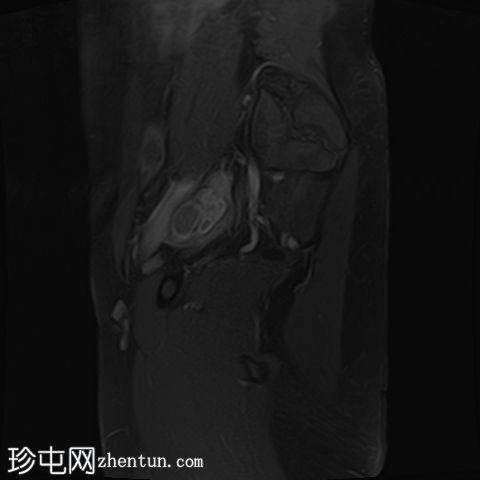

矢状位T1加权像

增强脂肪抑制像

在右侧附件区可见一较大病灶,最大轴位和头尾径约为3 x 3.8 x 3.7 cm。该病灶在T1加权像上呈高信号,脂肪抑制像上无信号抑制,在T2加权像上呈低信号(阴影效应)。病灶壁可见T2暗点征结节,增强扫描后未见明显强化。

此外,右侧附件区可见一扩张的管状结构,最大轴向和头尾径约6.3 x 2.1 x 5.2 cm。

该结构T1呈低至中等信号,T2呈高信号,分隔不完整。增强扫描未见明显强化,符合输卵管积水表现。

右侧道格拉斯窝内可见少量游离液体,可能为反应性积液。

所描述的右侧附件病灶具有典型的子宫内膜异位囊肿MRI特征,包括T1高信号(无脂肪抑制)和T2低信号(阴影)。T2暗点征的存在进一步支持慢性出血性内容物。

扩张的管状结构伴有T2高信号和不完全分隔,符合输卵管积水的表现,输卵管积水常见于盆腔子宫内膜异位症。少量邻近游离液体通常为反应性积液。